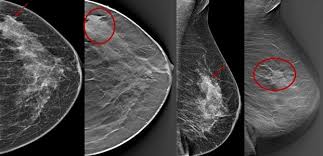

عکس ماموگرافی زنان

بعد از انجام ماموگرافی عکس ماموگرافی یا سی دی آن به شما تحویل داده می شود. عکس ماموگرافی بر اساس نوع دستگاه ماموگرافی و نمای تصویر برداری ظاهر متفاوتی دارد. نماهای مختلف ماموگرافی به تشخیص دقیق تر ضایعه کمک می کند. در ادامه چند نوع عکس ماموگرافی را مشاهده می کنید.